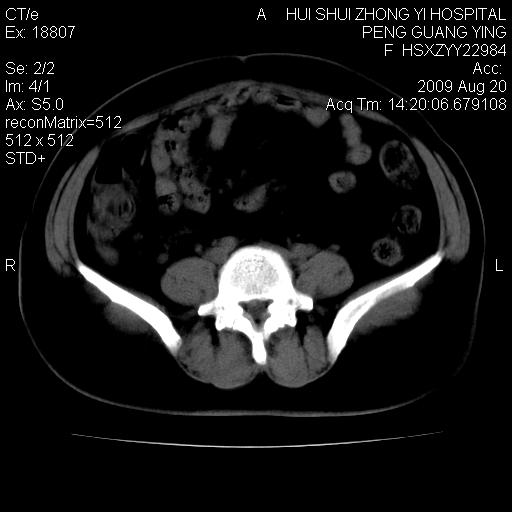

标题: CT21707:女,42岁,因发现下腹部包块2月。 [打印本页]

标题: CT21707:女,42岁,因发现下腹部包块2月。

目前的影像表现显示肿块位于腹腔及盆腔,但具体定位,分清来源较困难,是否来源于卵巢、子宫无法定论,子宫直肠及子宫膀胱周围脂肪间隙尚较清晰,如果患者有过腹腔好或者盆腔手术史,也可以形成不典型的血中,最好手术后定为定性,我期待结果。

软组织密度,与子宫一致。双侧卵巢形态、密度好,不支持来源于卵巢。